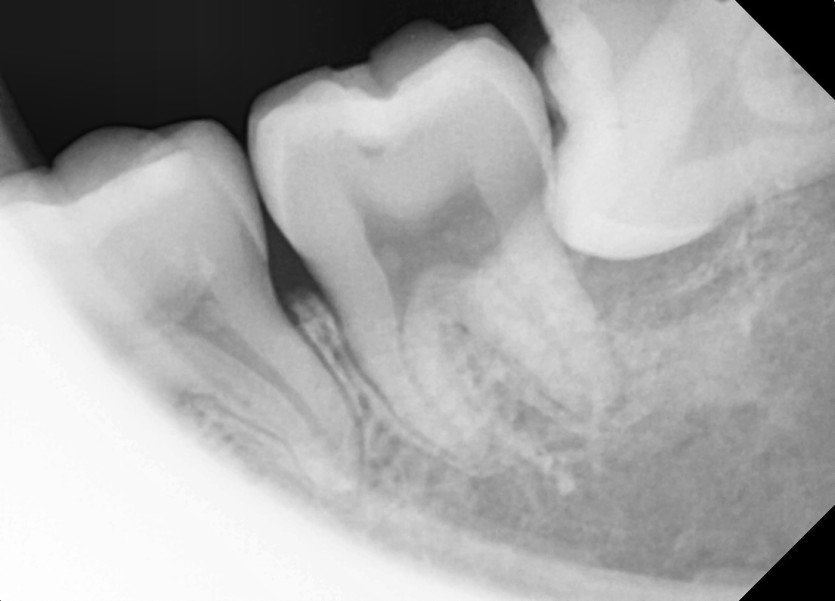

#28,38 사랑니 발치

구강 외과 전문의가 당일 발치했습니다.